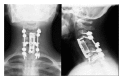

Aneurysmal bone cyst is a pseudotumoral lesion. Complete resection prior to selective arterial embolization seems to be the treatment of choice for the more extensive and destructive lesions. In these cases maintaining stability of the cervical spine is critical. This can be very challenging in children and adolescents in whom the axial skeleton is still growing. In this case a young girl presented with a voluminous cervical aneurysmal bone cyst encaging both vertebral arteries and spinal cord. The lesion was treated with aggressive surgical resection, followed by cervical vertebral fusion with instrumentation. After nine months the patient referred no pain and no neurological deficit. MRI scans showed an extensive local recurrence. The family of the young girl refused any other therapy and any other followup. The patients returned to our attention after five years with no pain and neurological deficit. Cervical spine radiographs and MRI scans showed a complete regression of the extensive local recurrence. In the literature, the possibility of spontaneous regression of residual part or local recurrence is reported. The case of this young girl provided the chance to attend a spontaneous regression in an extensive recurrence of aneurismal bone cyst.